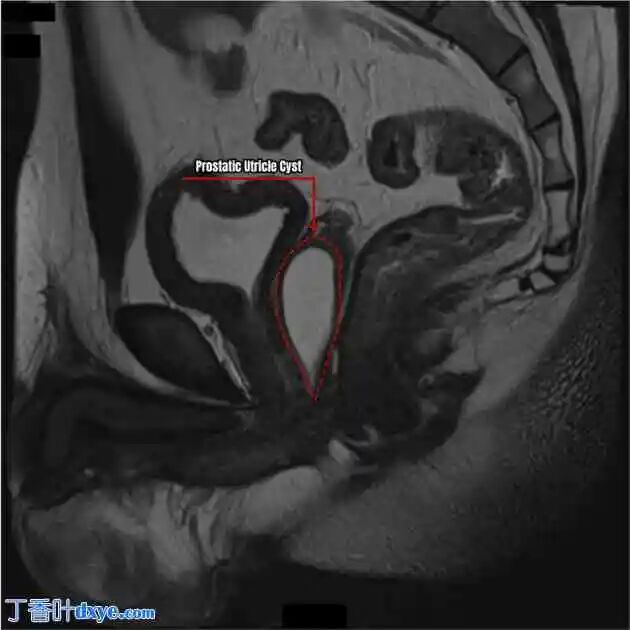

尿道下裂病史,婴儿期曾分两期手术矫正。此后,他一直患有复发性睾丸炎和尿路感染约10年。他的症状包括排尿困难、排尿不尽、尿频和复发性阴囊瘘。最初,患者对抗菌治疗反应良好;然而,症状频繁复发。复发症状最初被归因于尿道下裂修复术后阴茎尿道狭窄。患者采用颊黏膜移植矫正了狭窄。尽管狭窄得到矫正,但患者仍然持续出现复发性尿路感染和睾丸炎。 2018年进行的下腹部磁共振成像显示,一个大的中线囊性结构占据了整个前列腺,其大小为1.6 cm × 1.5 cm × 4.4 cm,未见弥漫受限的离散灶,提示为前列腺囊肿(图1)。阴囊纤维化,内容物为瘢痕组织和肉芽组织。双侧鞘膜积液很可能是继发于反复感染。患者被建议接受手术干预,但家属选择了最大程度的保守治疗。

图1

MRI T2加权矢状面显示,巨大的前列腺囊肿与直肠和膀胱的关系。